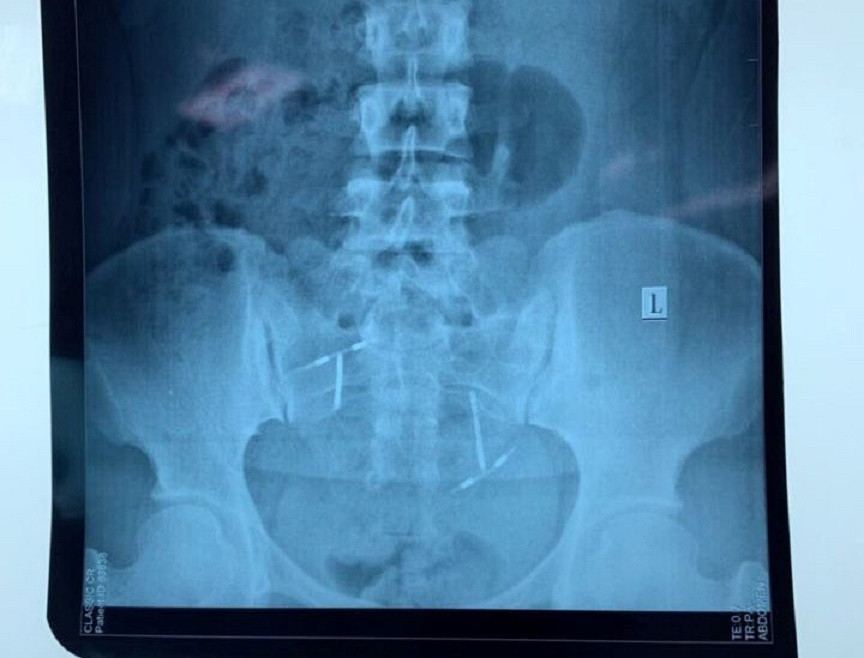

Vòng tránh thai "đi lạc" trong bàng quang của chị L.

Sau khi thực hiện các xét nghiệm thăm dò, chụp CT, chụp X-quang, hội chẩn các chuyên khoa…, các bác sĩ phát hiện dị vật nằm trong bàng quang của chị L.

Sau ca ca phẫu thuật kéo dài cả tiếng đồng hồ, ê-kíp bác sĩ của 2 khoa: Phụ sản và Ngoại Tổng hợp lấy ra vòng tranh thai hình chữ T trong bàng quang của bệnh nhân. Hiện, sức khỏe của bệnh nhân đang trong giai đoạn hồi phục và hoàn toàn tỉnh táo.